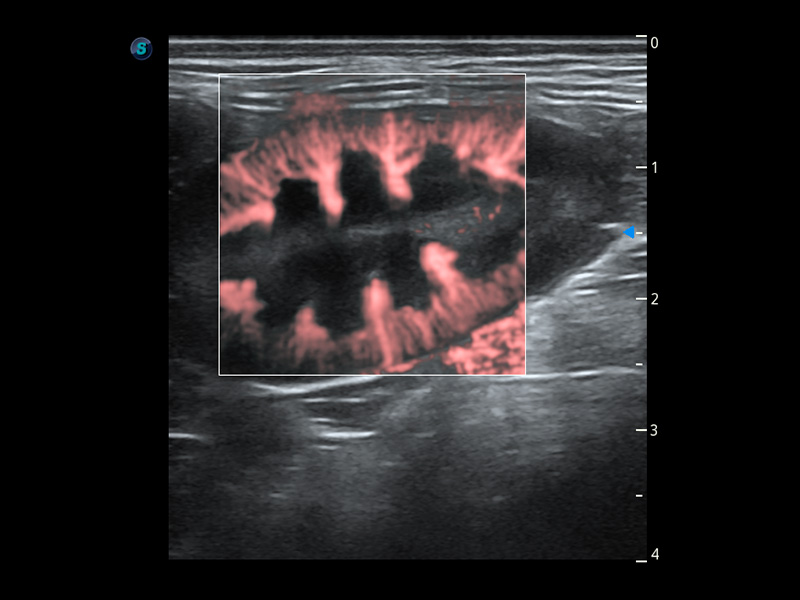

(猫)膀胱结晶

PDI 能量多普勒血流

提供高灵敏度和空间分辦率的血流图像,获得更加真实和丰富的诊断信息。